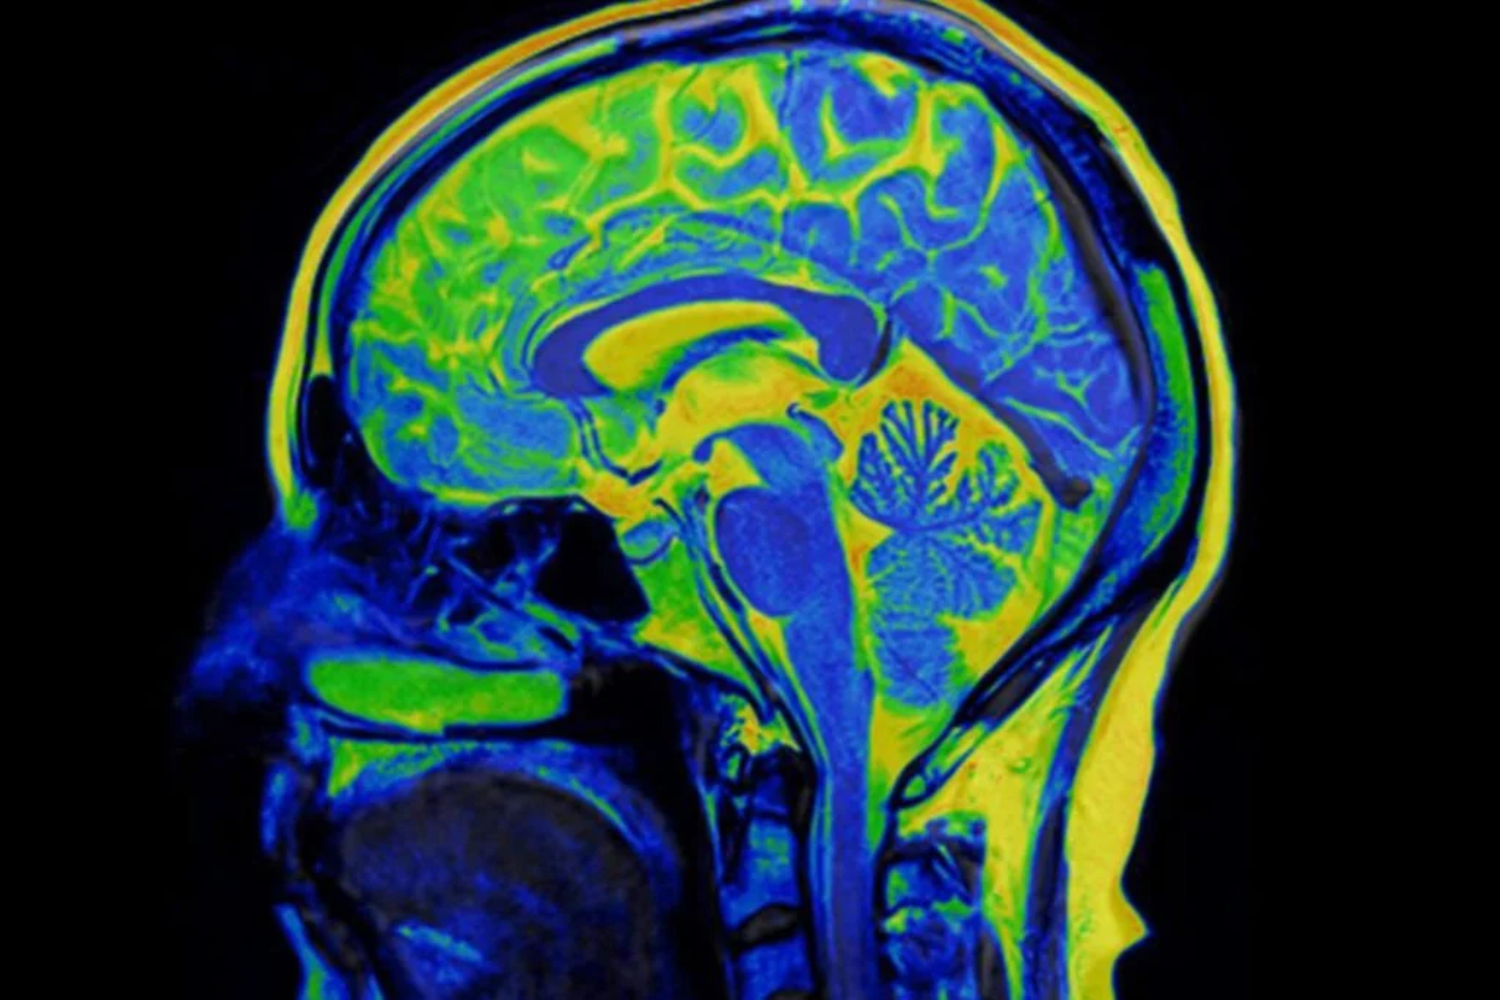

Como o DMT atua no cérebro

Revisões recentes também publicadas na Nature Medicine indicam que psicodélicos clássicos, como o DMT, atuam principalmente no receptor de serotonina 5-HT2A. Esse mecanismo promove alterações temporárias nos padrões rígidos de conectividade cerebral.

Em termos simples, o cérebro parece “flexibilizar” circuitos associados a pensamentos repetitivos e negativos — comuns na depressão. Após a experiência, observa-se uma janela de maior plasticidade psicológica, que pode facilitar mudanças emocionais e cognitivas quando combinada com psicoterapia.